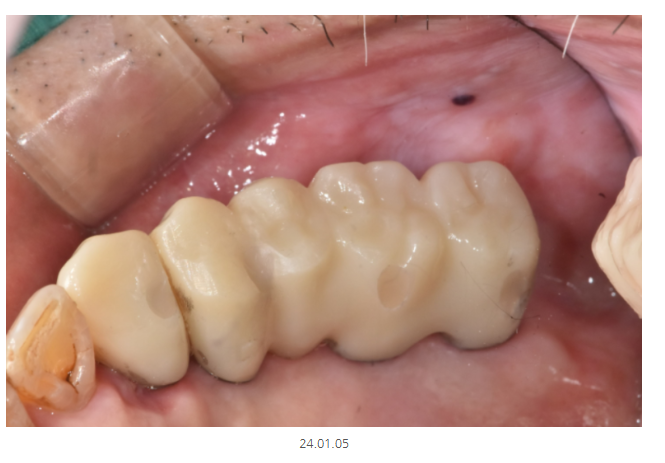

기둥을 디자인했으면

보철도 만들어야겠죠~?

바르디지털치과인만큼 모든 것을

디지털로 제작합니다!

완성 후 사진입니다.

70대 고령이시고

전신질환이 있어서 환자분이 걱정을 많이 하셨지만

무사히 끝냈습니다.